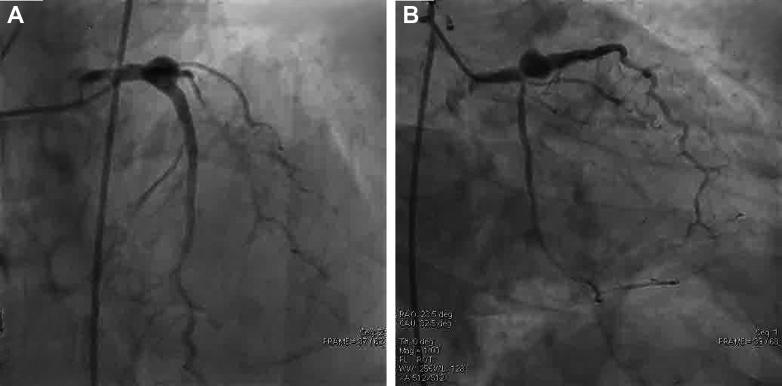

Coronary stent infection is a rare complication with a high mortality rate. We report a case of left anterior descending artery coronary stent infection and pseudoaneurysm that was successfully managed with timely intervention.

A middle-aged man who underwent a recent percutaneous coronary intervention (PCI) presented with fever and ischemic chest pain. Coronary angiography diagnosed coronary stent infection and pseudoaneurysm. The patient underwent successful emergency coronary artery bypass graft surgery with pseudoaneurysm resection and was successfully discharged.

TAKE-HOME MESSAGE: This case highlights that diagnosis of coronary stent infection requires a high degree of suspicion, and multimodality imaging helps in confirmation of diagnosis, early detection of life-threatening complications, and appropriate timely intervention.